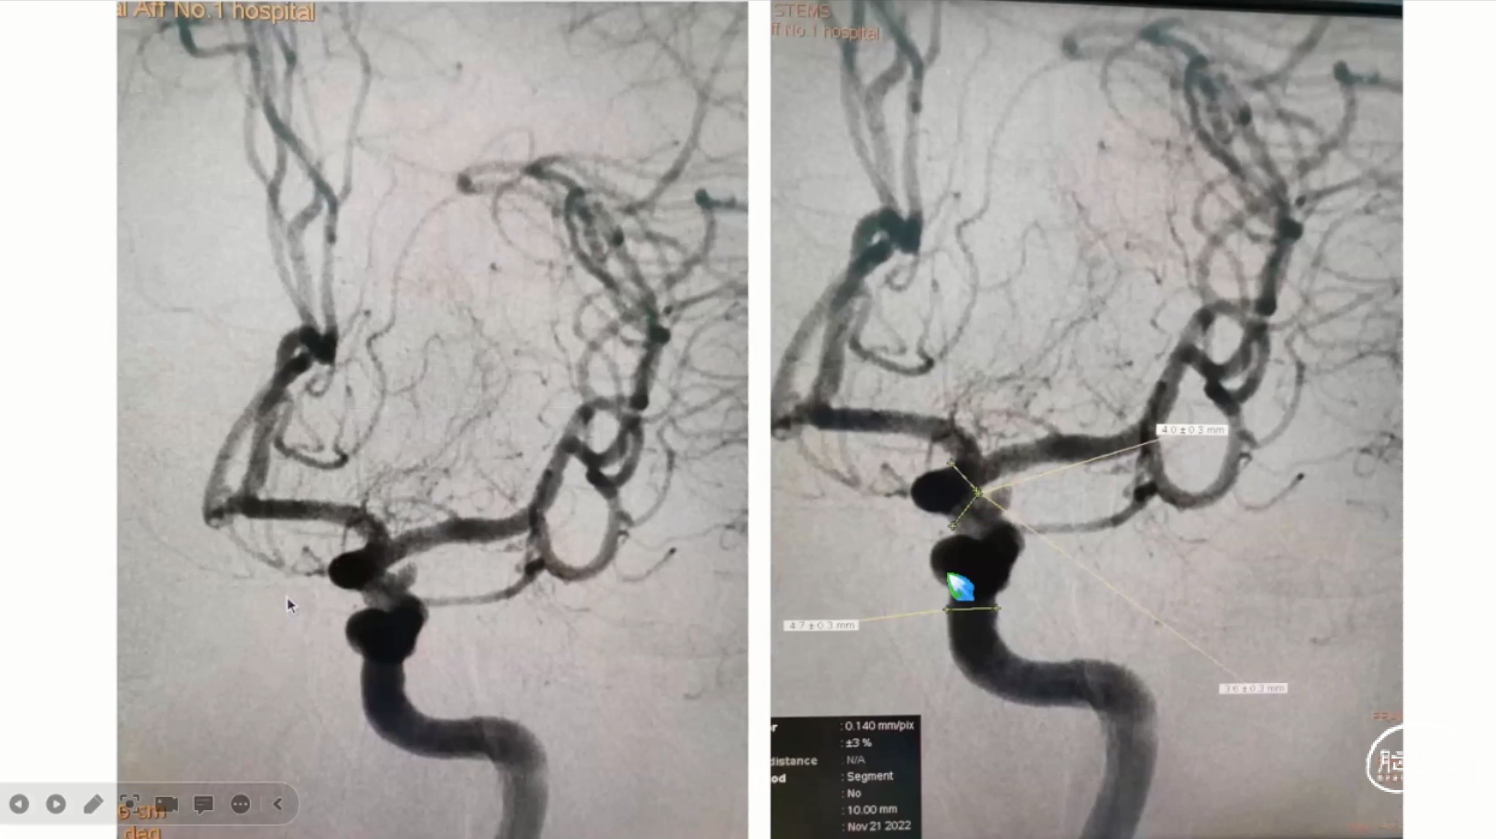

左侧椎动脉动脉瘤血流导向装置置入一例

哈尔滨医科大学附属第二医院 李永利教授团队